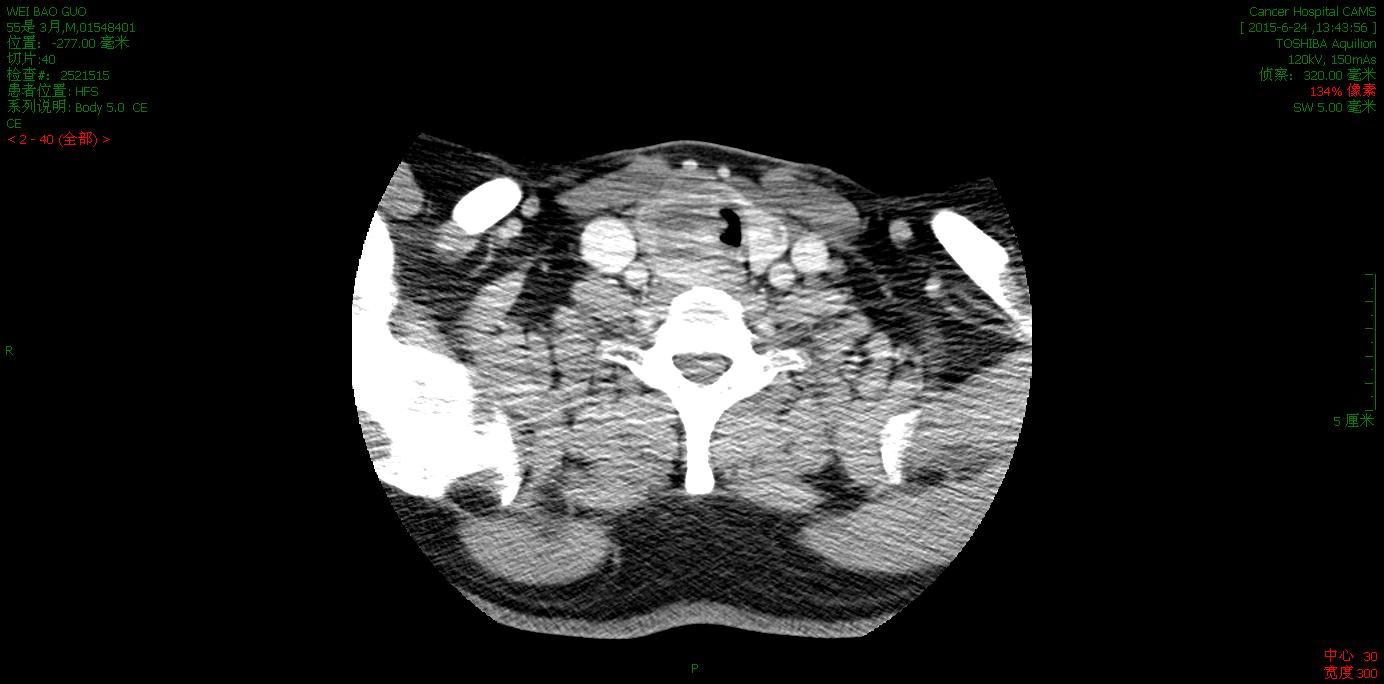

颈部或胸部CT

CT可以较为详细地展现检查者颈胸部的解剖结构和异常结构,对寻找声音嘶哑的原因非常有帮助。